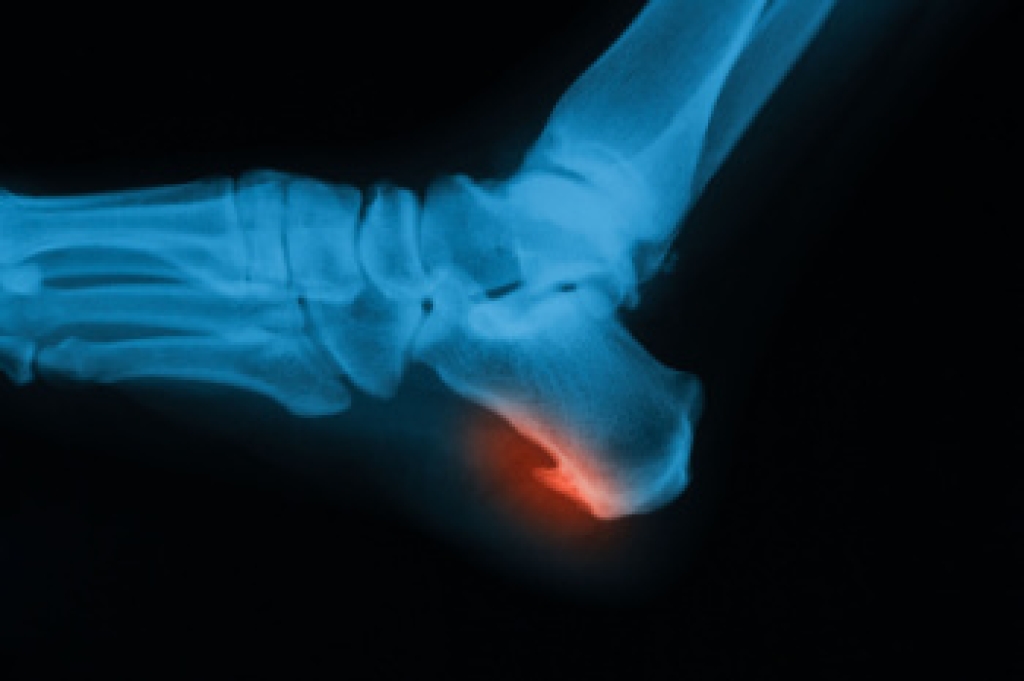

Diagnosis of cuboid syndrome is often difficult, and it is often misdiagnosed. X-rays, MRIs and CT scans often fail to properly show the cuboid subluxation. Although there isn’t a specific test used to diagnose cuboid syndrome, your podiatrist will usually check if pain is felt while pressing firmly on the cuboid bone of your foot.